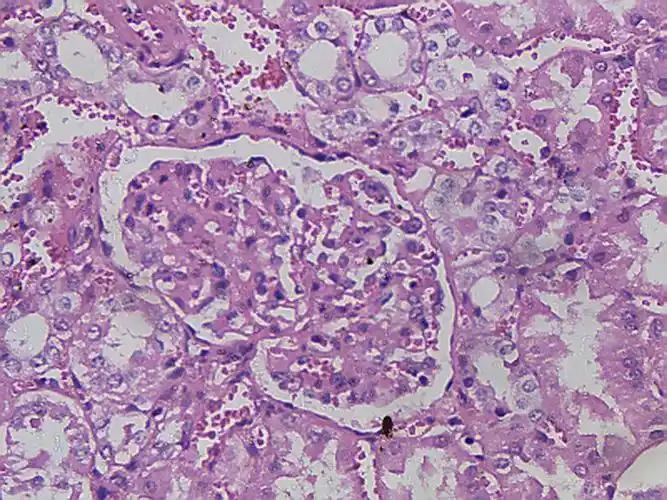

肾脏的光学显微镜照片

16mg/kg 剂量组的肾脏切片中,可以看到的病理特征包括:明显的肾间质炎

4mg/kg 剂量组的肾脏切片中,可以看到:部分肾间质炎性细胞浸润,部分肾

病理切片结果显示:部分肾脏出现肾间质炎性细胞浸润,远端肾小管扩张